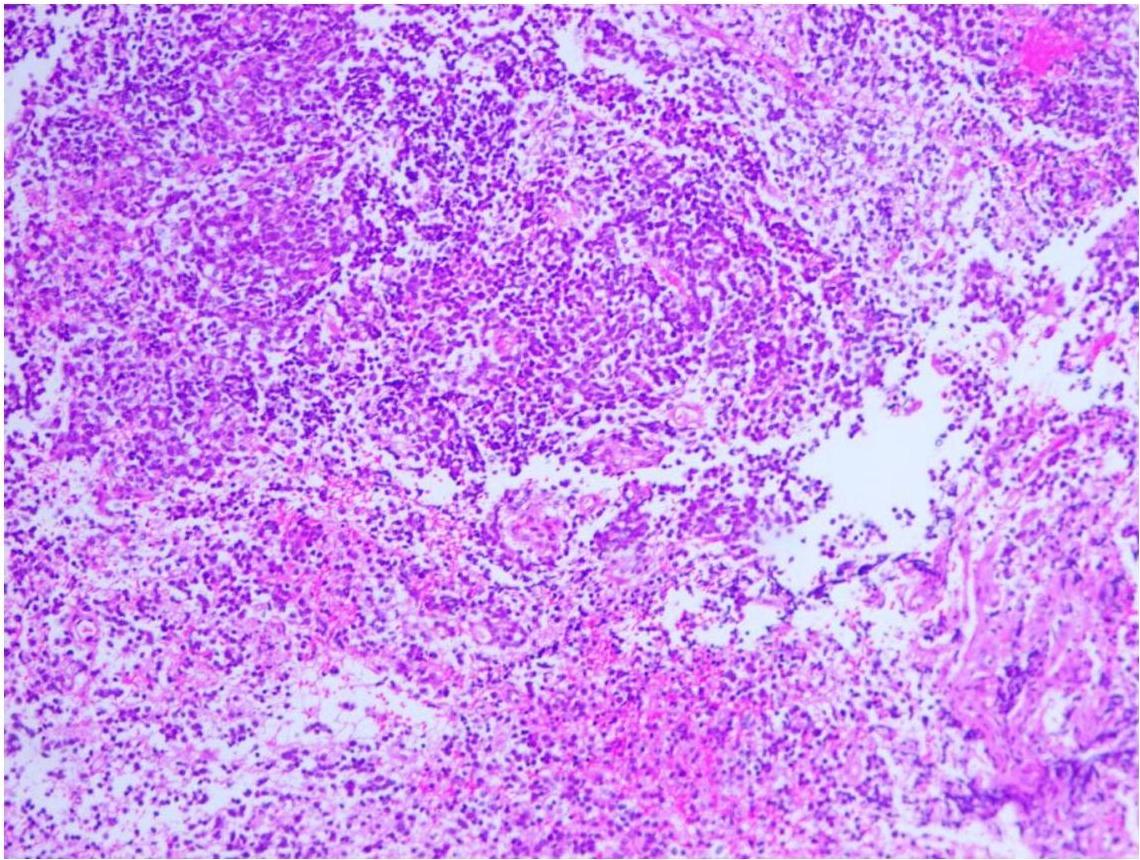

髓母细胞瘤的组织学分型常分为两种,分别是经典型与促纤维增生型。后者较多见。镜下特点为细胞排列紧密,体积较小,大小较一致,核大胞浆少,经典型可见菊形团样细胞排列结构,促纤维增生型中纤维组织增生明显,可见漩涡状及岛状结构,两者均有向神经细胞或胶质细胞分化的趋势。

瘤细胞体积较小,大小较一致,细胞核一般呈圆形或类圆形,细胞浆较少,部分细胞呈不典型的菊形团排列,核分裂像易见,部分区域的肿瘤细胞有神经分化趋势,间质纤维增生明显